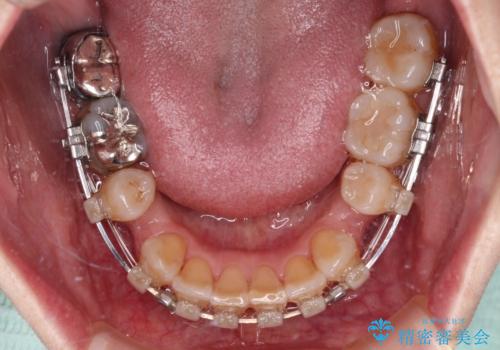

- 矯正装置

- クリアブラケット

第二小臼歯抜歯はイレギュラーな治療となるため、アンカースクリューを補助的に使用して、スムーズに治療を行えるように工夫をしました。